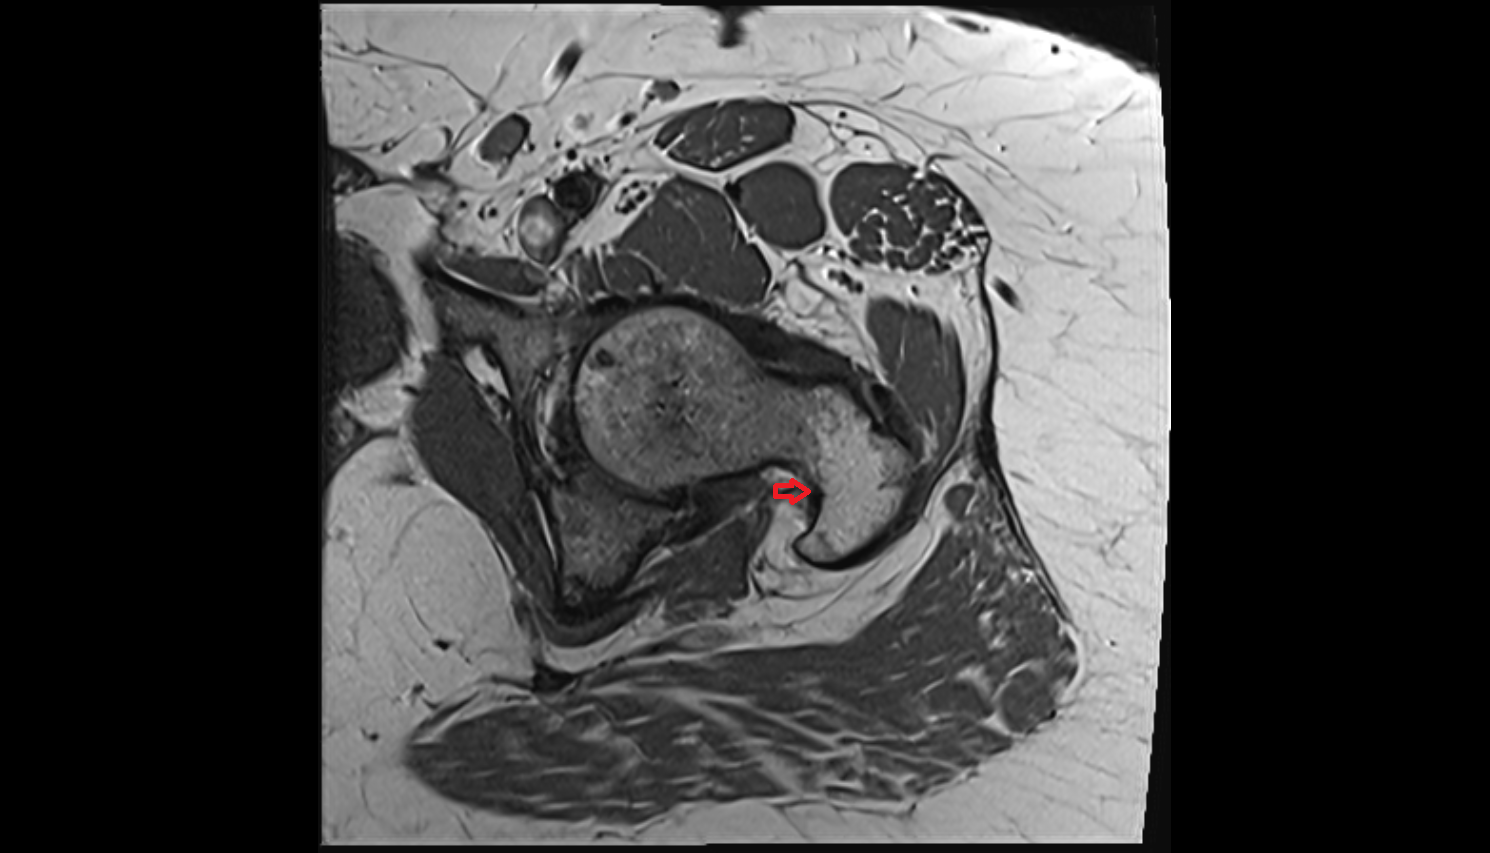

- Hip joint